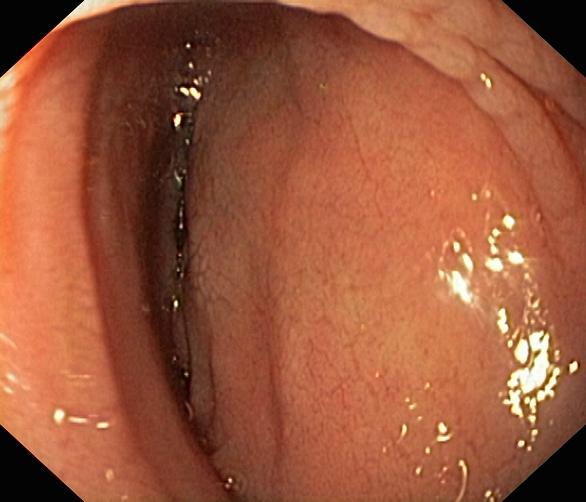

Celiakia